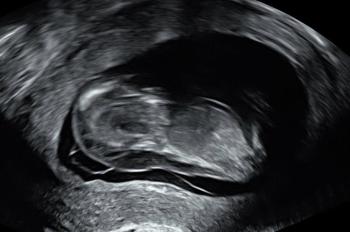

We went for our next scan at nearly 13 weeks pregnant and our baby was on the screen, their heart beating, moving their arms and kicking their legs about. Every scan where our baby was still alive was a relief, but this scan quickly changed and the sonographer started to tell us that there were lots of things wrong with our baby. There was a lot of fluid at the back of the neck, fluid all over her chest and a huge Cystic Hygroma on and around her head.

Baby scan